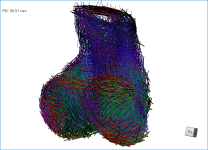

- Check the Use direction as color option.

Checking this option will re-code the vector map in accordance with the orientation of the vectors — red for the X axis, green for the Y axis, and blue for the Z axis.

- Apply clipping to evaluate inner surfaces (see Clipping).